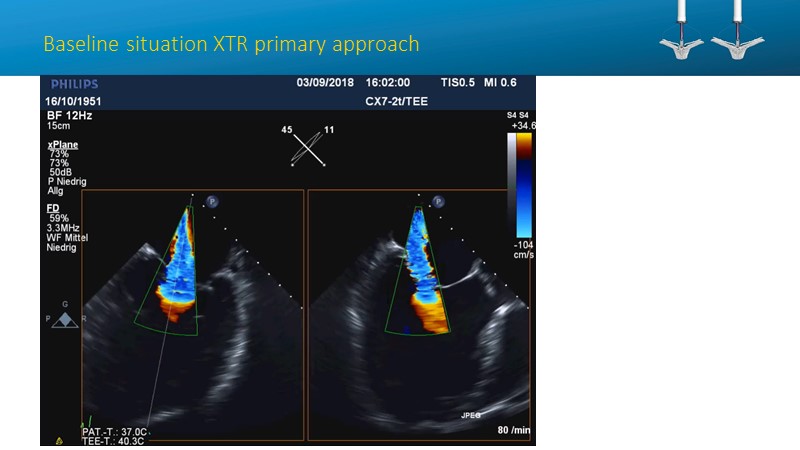

- To learn how will product innovation (Mitraclip NTR / XTR) drive improvement in procedural and clinical outcomes (EXPAND)